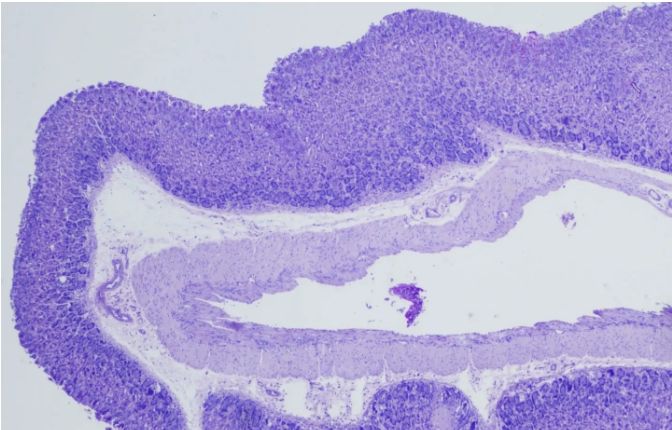

PAS染色實驗過程中常見問題解答由普拉特澤生物為大家總結分享。PAS染色作為一種在組織學中廣泛應用的染色技術,雖然具有高度的特異性和敏感性,但在實際操作過程中,也常會遇到一些問題和挑戰(zhàn)。本文是關于PAS染色實驗的最后一篇介紹,前面我們學習了PAS染色實驗材料有哪些?、PAS染色和mpo染色區(qū)別是什么?、PAS染色實驗注意事項以及PAS染色臨床應用,可以點擊標題直接傳送回去學習的哦。普拉特澤生物組織染色檢測平臺承接酵母雙雜實驗外包上百例,早就為大家把實驗過程中要踩的雷、吃的虧幫大家吃完了,現在我們就來看看,PAS染色中常見問題的解答:

綜上所述,PAS染色雖然是一種常用的組織學染色方法,但在實際操作中常常會遇到一些問題。通過掌握常見問題及其解決方法,我們可以更好地應用這項技術,提高染色效果和觀察結果的準確性。同時,不斷學習和實踐也是提高PAS染色技術水平的重要途徑。